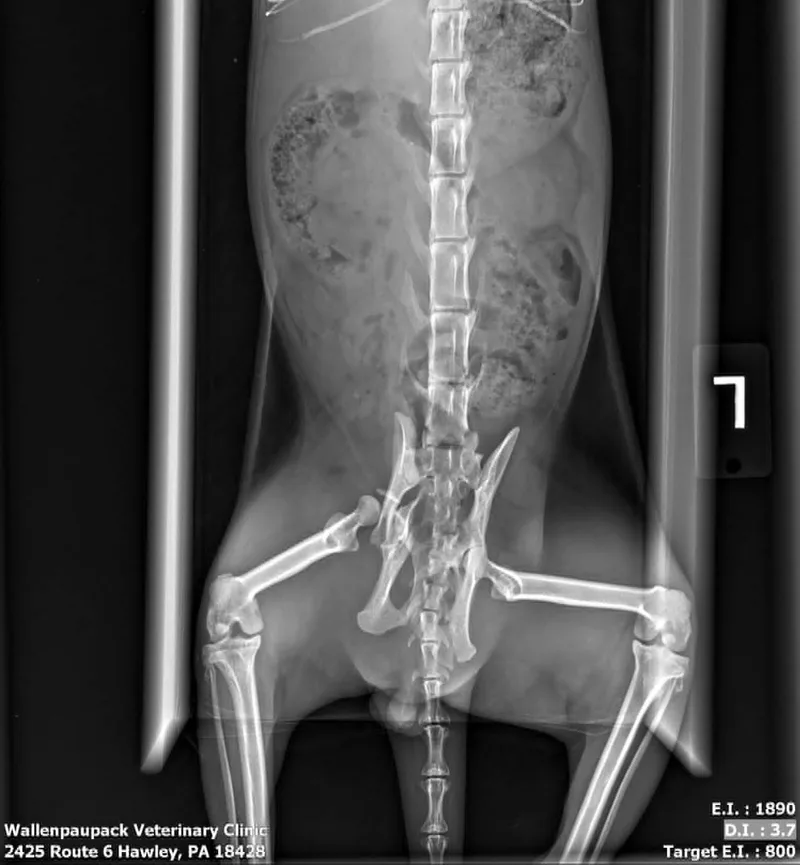

Brave Heart, a Scottish Fold, was rescued mid-November 2025 with a broken pelvis and a dislocated right hind leg. He also had puncture wounds on his right hind leg. The trauma that caused his injuries is unknown, but the most likely cause would be a predatory attack. Brave Heart required surgery called a FHO (femoral head ostomy) to save his leg and restore his ability to walk. He was rushed to Eastern PA Veterinary Hospital in Allentown PA. Brave Heart's surgery was performed on November 26th and he came back to his foster home on Thanksgiving. Brave Heart required 2 months of physical therapy to return to full function. He has no limitations although you can see differences in his gait and stair climbing from "normal". Despite all that he has been through, Brave Heart remains a sweet loving guy, who purrs easily and craves belly rubs. He has been ready for a forever home for a while now; however, his foster family has been reluctant to let him go. They acknowledge that in order to get the attention that he deserves, Brave requires a home as an only cat or with one or two other cats. He seems to perk up when grandchildren are around, but does retreat to a quiet area if they are too rambunctious. Brave does not hesitate to let the other cats know that he is "royalty" and expects respect. Despite his size, he does not back off if confronted. He can also be quite vocal if his meals are late or he feels unappreciated. He is often called "Little Prince" and is deeply loved by his human subjects.